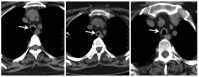

A 50-year-old female patient was evaluated at our center in February 2016 with history of hearing loss, inflammatory arthritis, and saddle nose for four years and new-onset worsening of hoarseness of voice, cough and breathlessness for three months. She was being treated as GPA based on clinical features and anti-myeloperoxidase (MPO) positivity with oral steroids and weekly methotrexate of 22.5 mg. Further evaluation showed normal complete blood count but raised erythrocyte sedimentation rate with normal urine examination, renal functions and liver functions. Chest X-ray did not show any infiltrates. Cardiac evaluation was normal. High-resolution computed tomography (HRCT) of the chest with neck cuts showed circumferential thickening of trachea (Figure 1).

In January 2017, she presented with two- week history of worsening of shortness of breath, wheeze and stridor. Further evaluation showed interval increase in circumferential thickening of trachea and bilateral main stem and lobar bronchi on HRCT of the chest and neck. However, repeat ANCA was negative for both proteinase 3 and MPO by line immunoassay and by indirect immunofluorescence for cytoplasmic and peri-nuclear ANCA. After initial treatment with broad-spectrum antibiotics and increased steroid dose, she had a marginal improvement. Considering this as a disease relapse, she was given rituximab 2 g two weeks apart. At subsequent follow-ups, the patient was doing well with just oral prednisolone 5 mg daily. At fourth month follow-up, HRCT of the chest with neck cuts was repeated and it showed reduction in wall thickening as compared to the previous scans (Figure 2). This time, the patient was given early rituximab 500 mg maintenance therapy and discharged on same dose of oral prednisolone and cotrimoxazole.